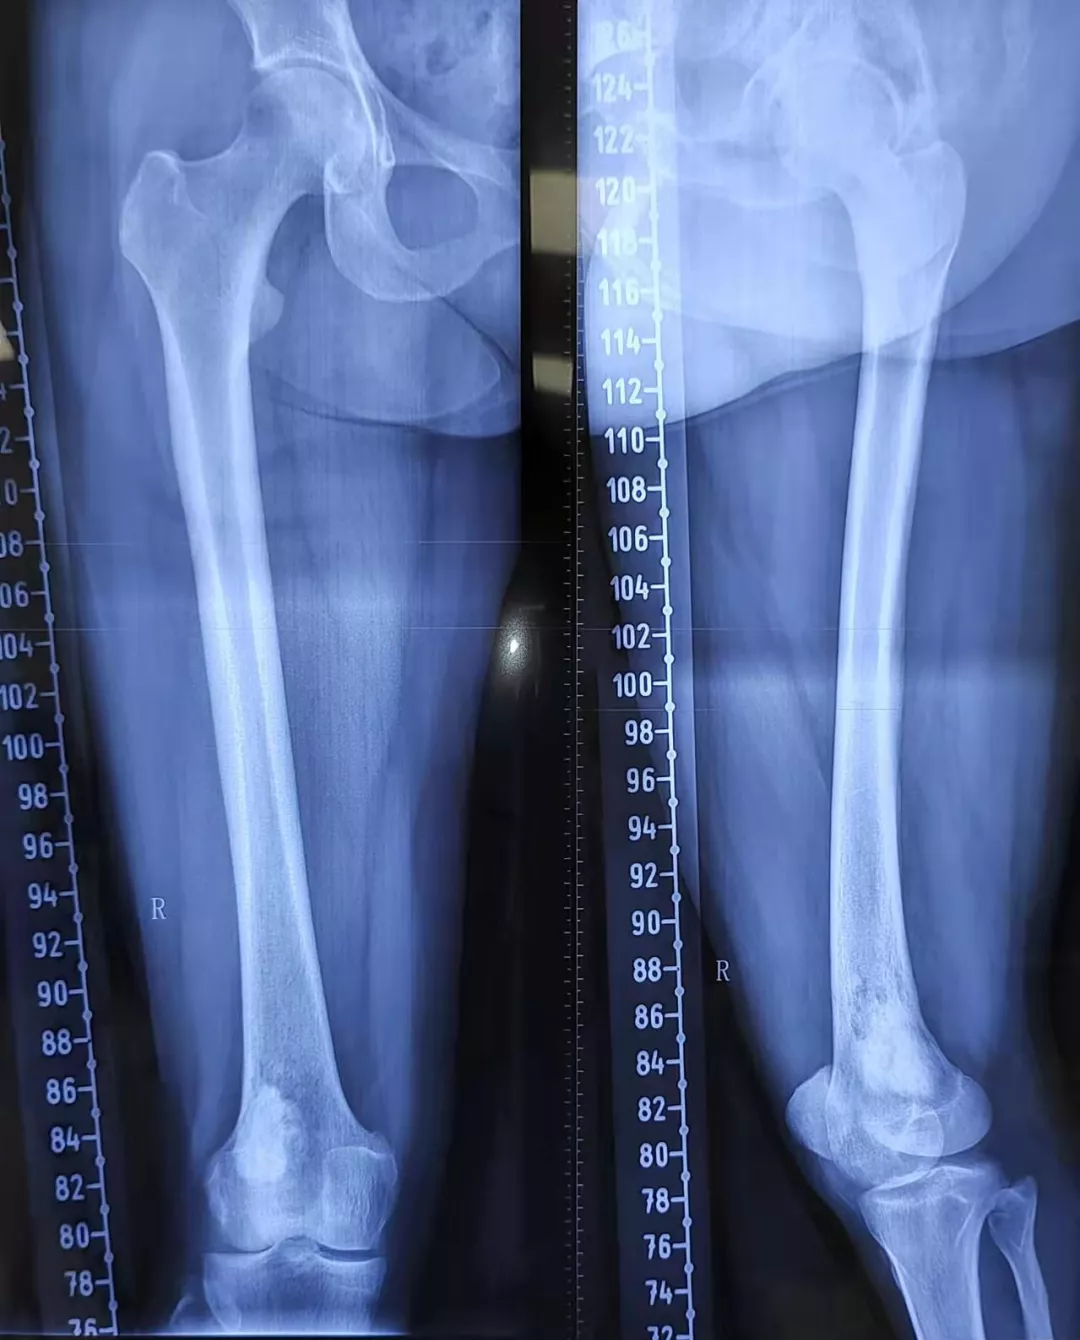

右股骨远端骨肿瘤

股骨远端骨肿瘤

【请教】右股骨远端肿瘤

股骨下段巨大占位,良性?恶性?